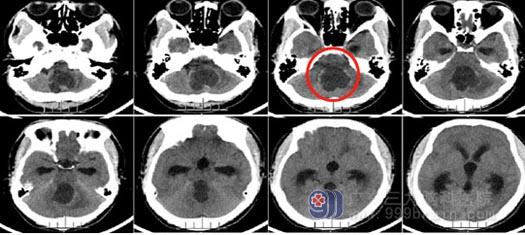

▲术前CT

26岁的小洪,半个月前出现头痛、头晕和轻微的吞咽困难,他没在意,觉得可能是没有休息好造成的。可随着时间的推移,这些症状不但没有好转,反而明显加重,走路都开始摇摇晃晃了。当地医院头颅CT检查提示“小脑蚓部及四脑室占位并梗阻性脑积水”,医生建议转院治疗。

小洪所患的很大可能是血管母细胞瘤,这是由脑神经和脊髓神经所产生的一种高度血管分化的良性肿瘤,血供非常丰富,手术中一旦出血,将会异常凶猛,难以控制,远非一般肿瘤手术可比,再加之小洪的肿瘤长在小脑和脑干中间,紧贴延髓,这是人体的呼吸中枢,万一损伤后果不堪设想,这无疑给手术又增加了一层难度。

医院副院长、神经外五科主任鲁明指示,患者为起源小脑蚓部突入四脑室的血管母细胞瘤,无家族史,腹部CT及全脊髓未见病变,考虑颅内单发病变。此肿瘤血管异常丰富,需要术前准确判断及术前的充分准备,更需要术中的精湛技术,才能避免大出血或切除不彻底情况。术后仍需注意再出血风险,同时肿瘤位置位于脑干背面,应尽可能避免脑干损伤,还要关注术后脑积水缓解情况。